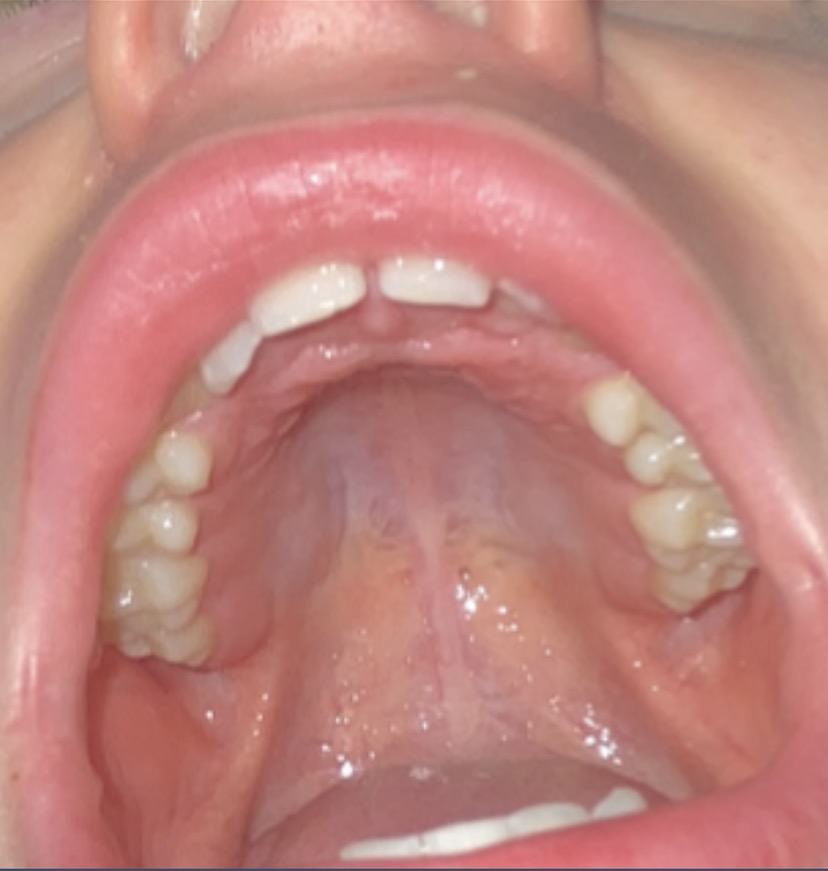

Have an ortho visit soon. Any advice before hand on what I need to get fixed, I have a cross bite and crooked teeth. Your not medical professionals but do you have advice if I should do orthtropics or dontics

IMG 0954